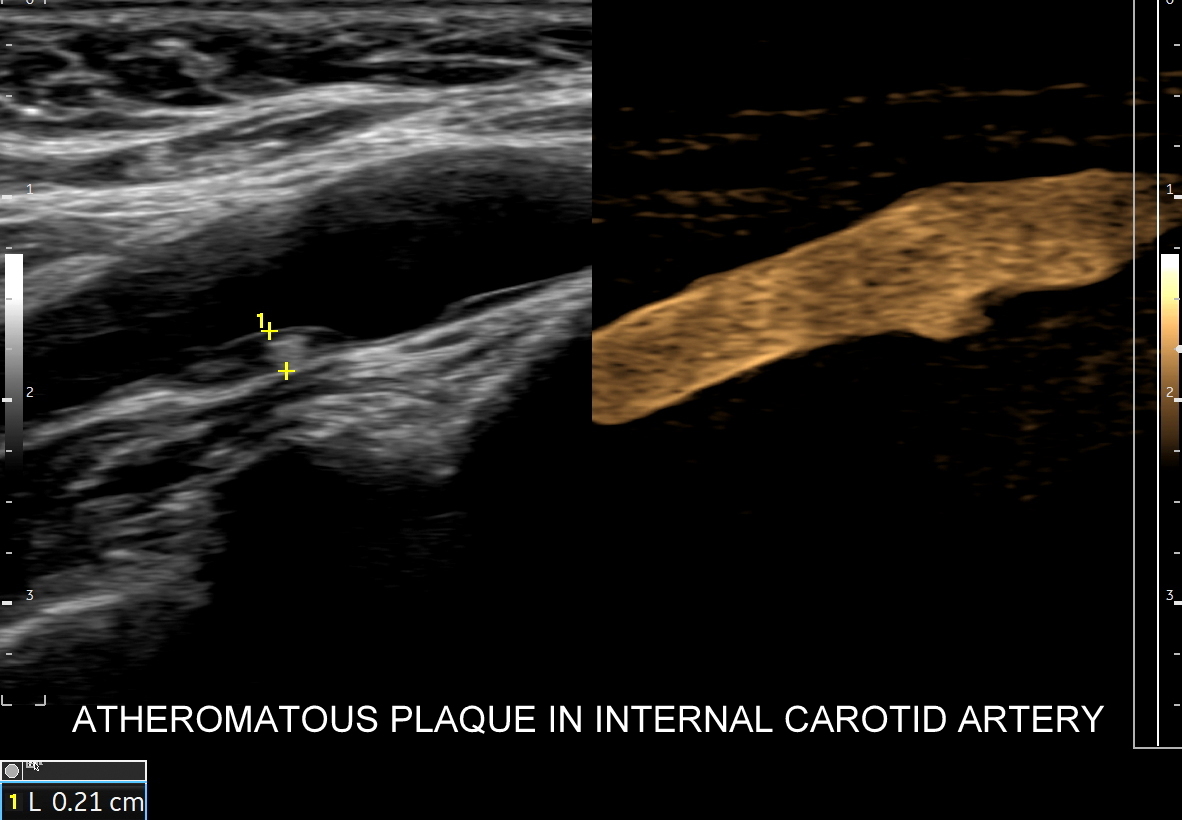

Tryb B-flow wyjątkowo korzystnie sprawdza się także przy badaniu wnętrza dużych i średnich naczyń. Otóż umożliwia on pewne zobrazowanie drożności naczynia, umożliwia wykazanie obecności / lokalizacji naczynia przy niesprzyjających warunkach obrazowania w trybie B, a poza tym uzyskiwane w omawianym trybie obrazy zarysów błony wewnętrznej naczyń (np. tętniczych blaszek miażdżycowych, skrzeplin przyściennych, zmian w przebiegu dysplazji włóknisto-mięśniowej, czy zapaleń tętnic) charakteryzują się wysoką rozdzielczością i kontrastowością. Skany dużych naczyń w trybie B-flow przypominają wręcz te uzyskiwane w klasycznej angiografii opartej o promieniowanie rentgenowskie. B-flow wykorzystywany może być praktycznie i rutynowo do obrazowania naczyń szyi i kończyn, naczyń wątroby, naczyń trzewnych, nerkowych oraz dużych naczyń brzusznych.